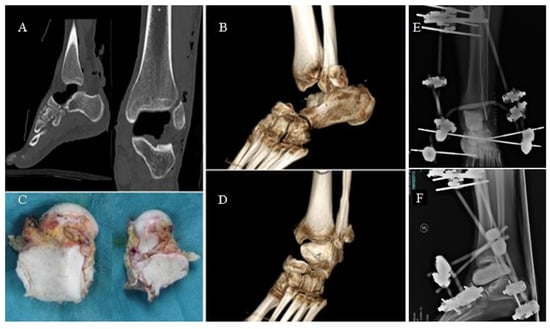

A 27-year-old male patient suffered a road accident in September 2013, reporting a superficial traumatic head injury and a left fibular fracture with an open wound and complete enucleation of the left talus. The missing talus was collected: It presented minor osteochondral injuries in the medial part and macroscopic contamination but was not fractured. After primary care, the wound on the foot and ankle was washed and debrided, and an antibiotic-coated cement spacer was applied to fill the void left by the talar enucleation (Figure 1). The fibula was stabilized using K-wires, and an external fixator was applied to maintain the stability of the ankle. The talar void was filled by a gentamicin/clindamycin-loaded cement spacer (Figure 1).

Figure 1.

CT images (A) and volume rendering (B,D) showing the gap left by the talus (C). External fixation of the ankle joint (E,F).